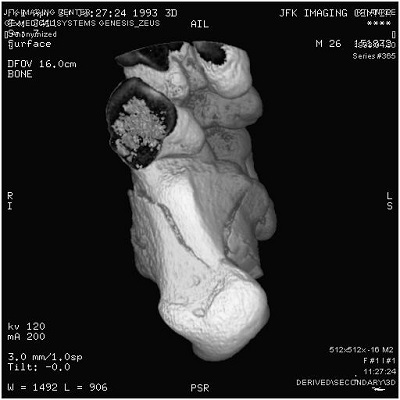

In most DICOM software, pressing the mouse button and dragging it left and right should allow you to control window width, and dragging it up or down should control the level. On other software, there might be two controls side by side which are marked W and L (always read your product documentation to be safe). See screen capture below from OsiriX software running on my machine at home showing the Window Width and Level functionality on a DICOM image.To sum up, a radiological workstation monitor would have permitted you to see all 65,536 shades of gray at once, but in a conventional monitor, or a cell phone for example, you will use W/L functions to navigate the entire range in small sized chunks at a time adjusting for the body part you want to zone in as well as adjusting for the viewing monitor’s capabilities and the user’s eye comfort at the same time. Most software will have presets for head, lung, etc to enable the radiologist to select these ranges quickly at the same time providing him/her with the ability to override these settings when necessary. Pretty cool, huh?